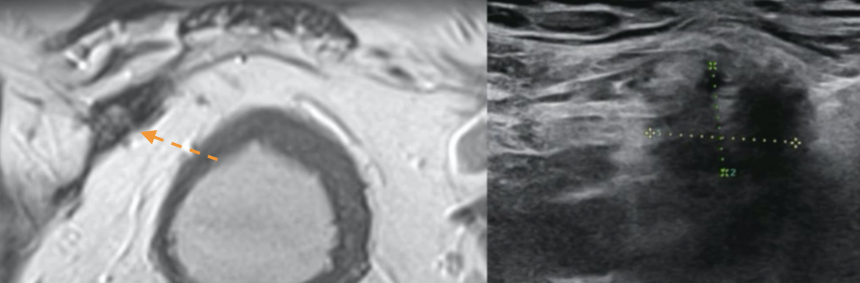

Récidive en bord de filet

Filet qui masque tout

Aspect ondulé

Retraction nodulaire pathologique

Filet au CT